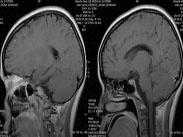

結核性腦膜炎癥狀

• 結核性腦膜炎

628健康網為您分享有關結核性腦膜炎的癥狀,結核性腦膜炎的治療方法,結核性腦膜炎的預防知識,結核性腦膜炎的癥狀圖片,結...